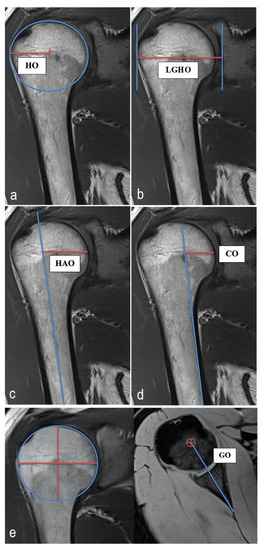

2.4. MRI Analysis, Parameters and Methods of Measurement